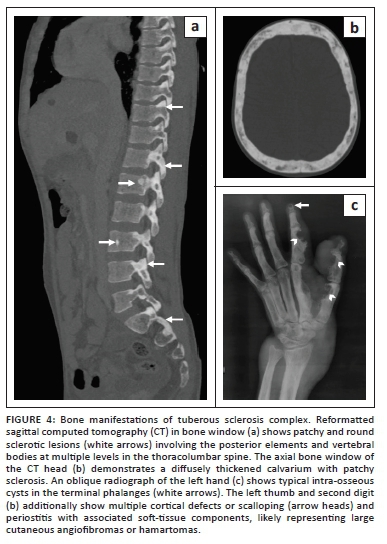

The study was extended to include computed tomography (CT) imaging of the brain and chest. A CECT scan of the brain revealed multiple cerebral and cerebellar calicified, as well as non-calcified cortical tubers, subependymal calcified nodules and a large cystic lesion with an enhancing mural nodule in the subependymal region of the frontal horn of the right lateral ventricle, consistent with a subependymal giant cell tumour (Figure 3). A CECT of the thorax was performed to evaluate for thoracic manifestations of TSC, revealing multiple, round, thin-walled cysts and a few small randomly distributed nodules uniformly scattered across both lungs, without any pneumothorax or chylous effusions. The findings were consistent with lymphangioleiomyomatosis (LAM) and multifocal micronodular pneumocyte hyperplasia (Figure 3). Bones showed diffuse calvarial thickening and sclerotic foci in the vertebrae, as well as in the pelvis.

Radiographs of the left hand depicted phalangeal intra-osseous cysts and a large soft-tissue mass causing scalloping of the cortex in the underlying digits (Figure 4).